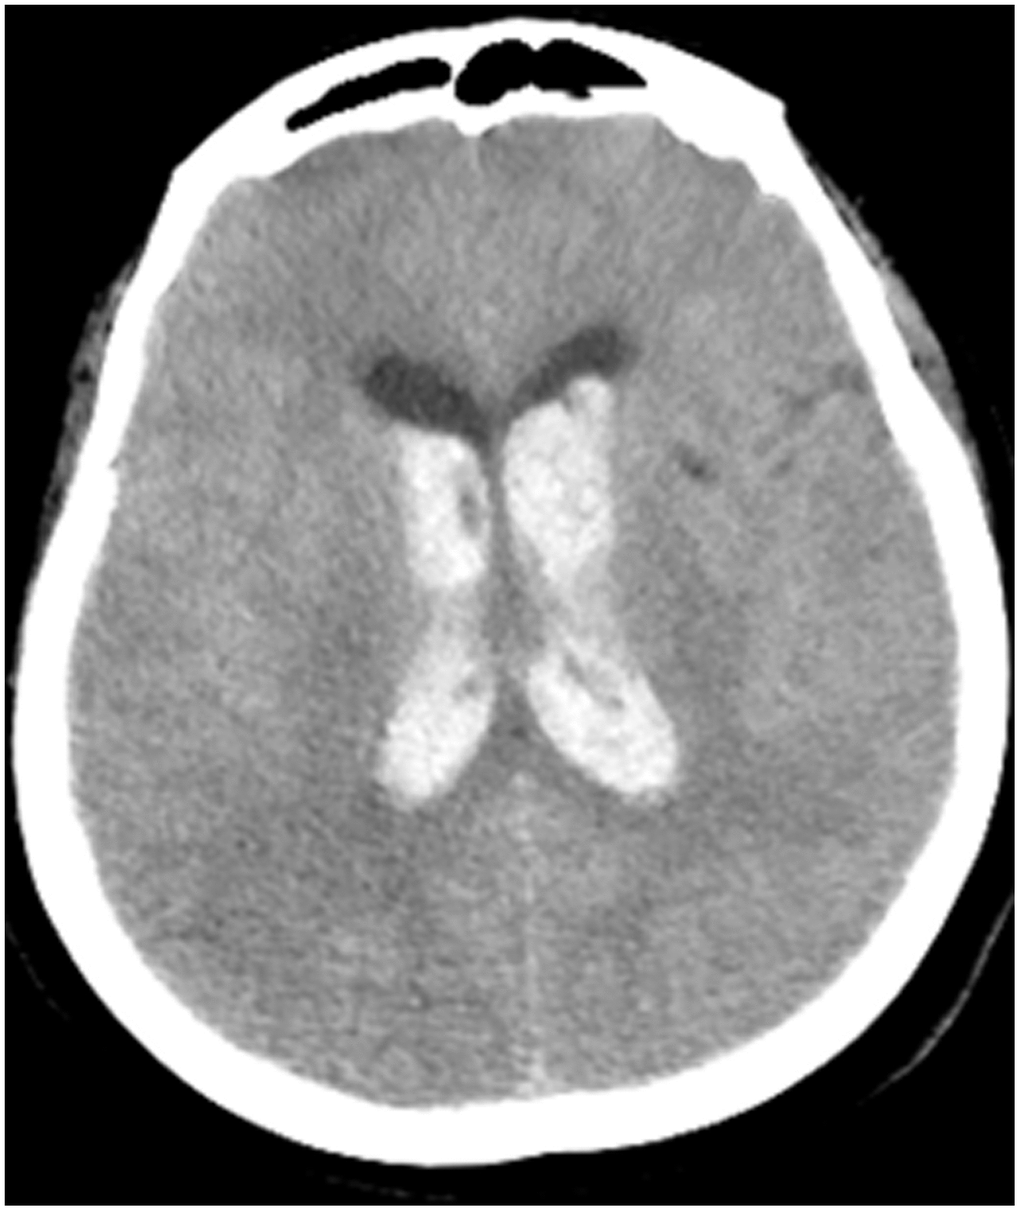

All patients were positive for the coronavirus nucleic acid test from pharyngeal swabs or blood. The blood lymphocyte counts and proportions of all patients were lower than normal (0.8×109/L) at the time of admission, and the white blood cell counts and proportions of six patients were higher than normal value (10×109/L). The blood D-dimer levels in all patients were higher than normal value (243 ng/mL) before neurological symptoms, and the C-reactive protein values in all patients were also higher than normal value (8000 μg/L). The chest CT of all patients showed flaky or frosted glass like- high-density shadow in lungs (Figures 1, 2), pleural effusion was seen in 2 cases (Figure 3), and no obvious abnormalities in 4 cases. The head CT imaging indicated that one patient had brainstem hemorrhage with ventricular cast and hydrocephalus (Figure 4), two patients had a large area of uniform low-density shadow on the frontotemporal lobe on the head CT (Figure 5), four patients had multiple flaky low-density shadow on the parietal lobe (Figure 6), one patient showed flaky low-density shadow in the pons (Figure 7), and three patients could see point-like low density shadow in basal ganglia (Figure 8).

Figure 4. Case 3, head CT imaging: one patient had brainstem hemorrhage with ventricular cast and hydrocephalus.

In this study, the patient with cerebral hemorrhage (case 3) received surgical treatment only 15 hours after CT examination, while 2 patients with large-area infarction (case 1, 2) missed the time window for intravascular treatment. Thus, it is necessary to establish a set of plans in advance for responding to acute stroke in the hospital and to improve the related personnel and equipment configuration, or to establish a fast, safe, and controllable transfer mechanism according to different conditions in the epidemic area.